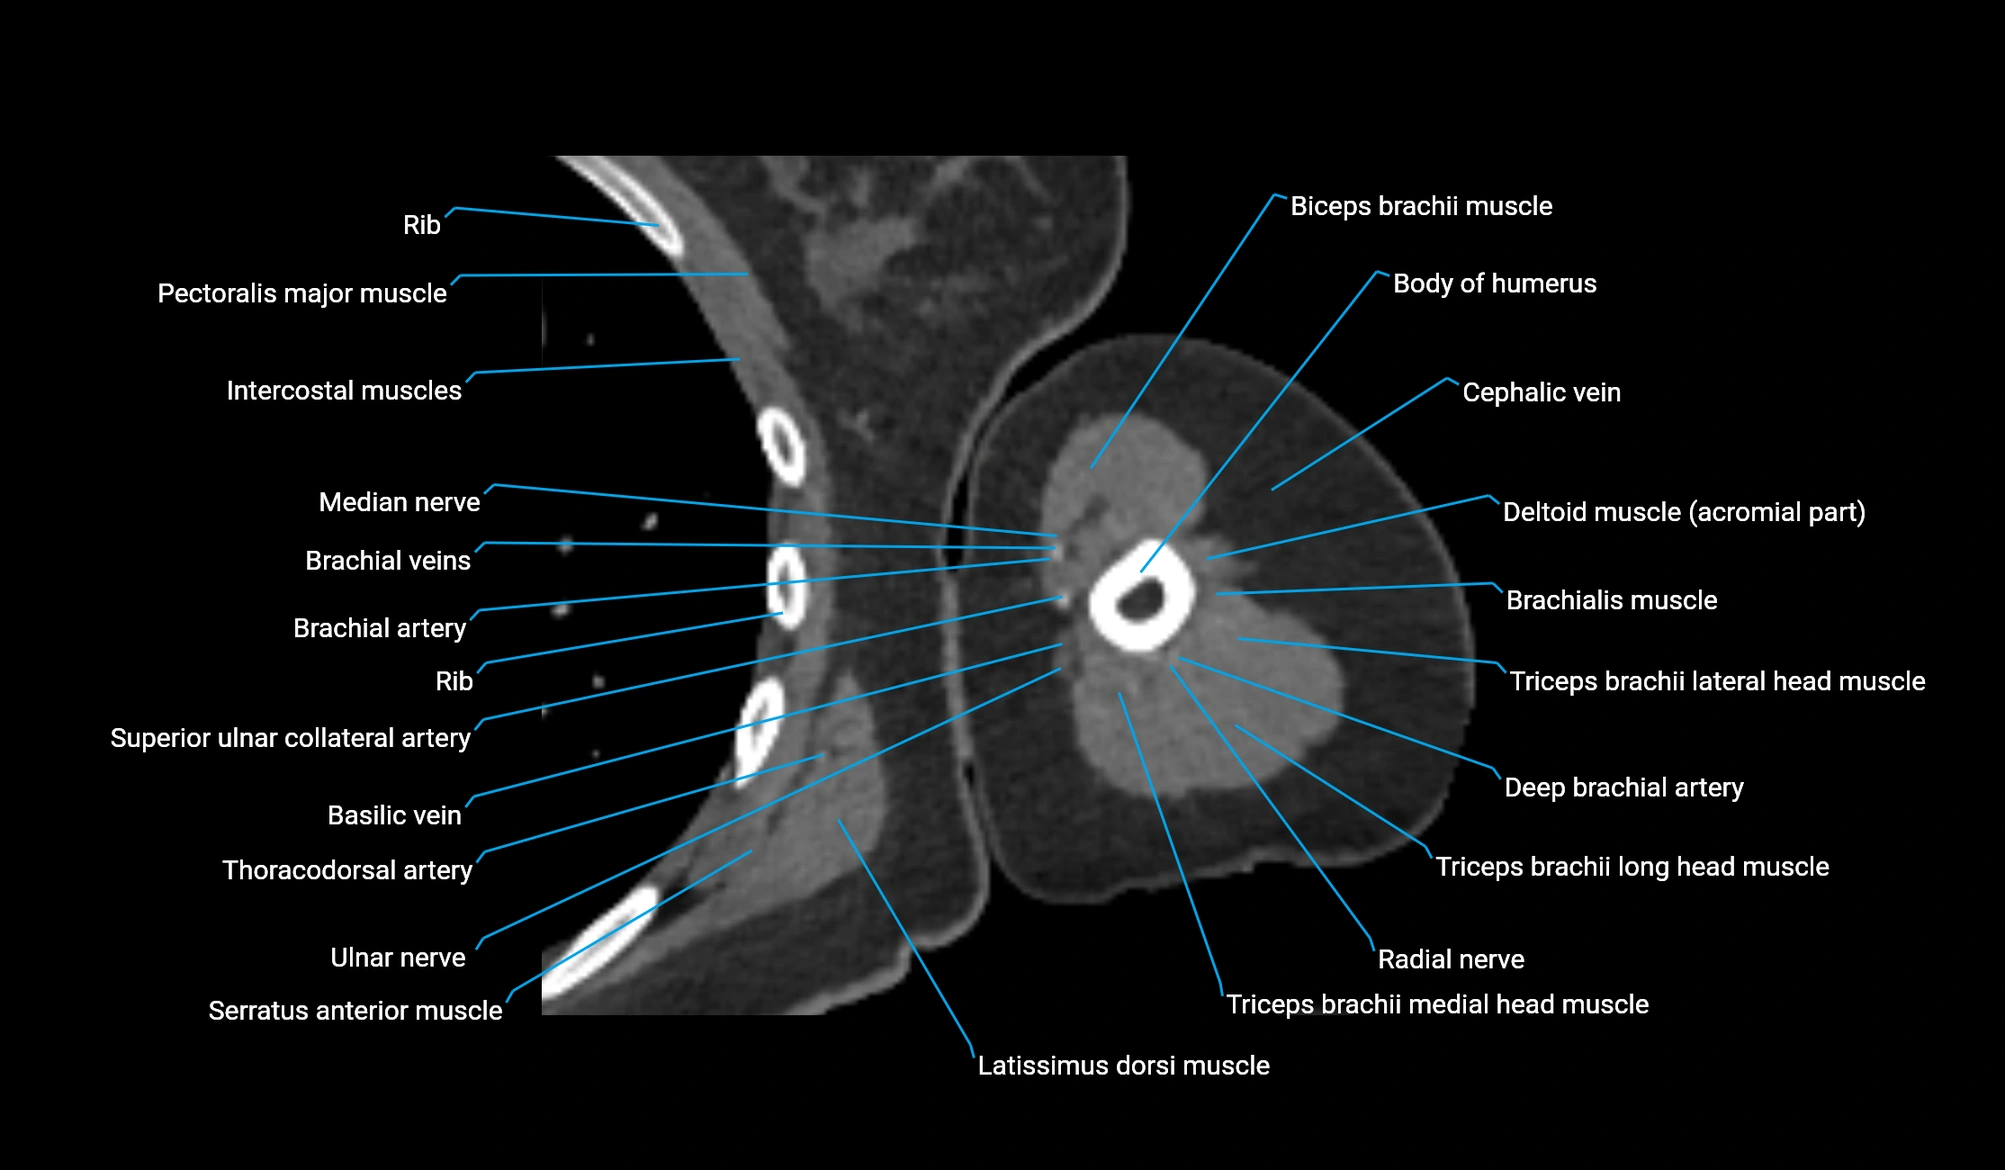

- Biceps brachii muscle

- Brachialis muscle

- Body of humerus

- Cephalic vein

- Brachial artery

- Basilic vein

- Median nerve

- Radial nerve

- Ulnar nerve

- Long head of triceps brachii muscle

- Lateral head of triceps brachii muscle

- Medial head of triceps brachii muscle

- Deep brachial artery

- Superior ulnar collateral artery

- Thoracodorsal artery

- Acromial part of deltoid muscle

- Pectoralis major muscle

- Latissimus dorsi tendon